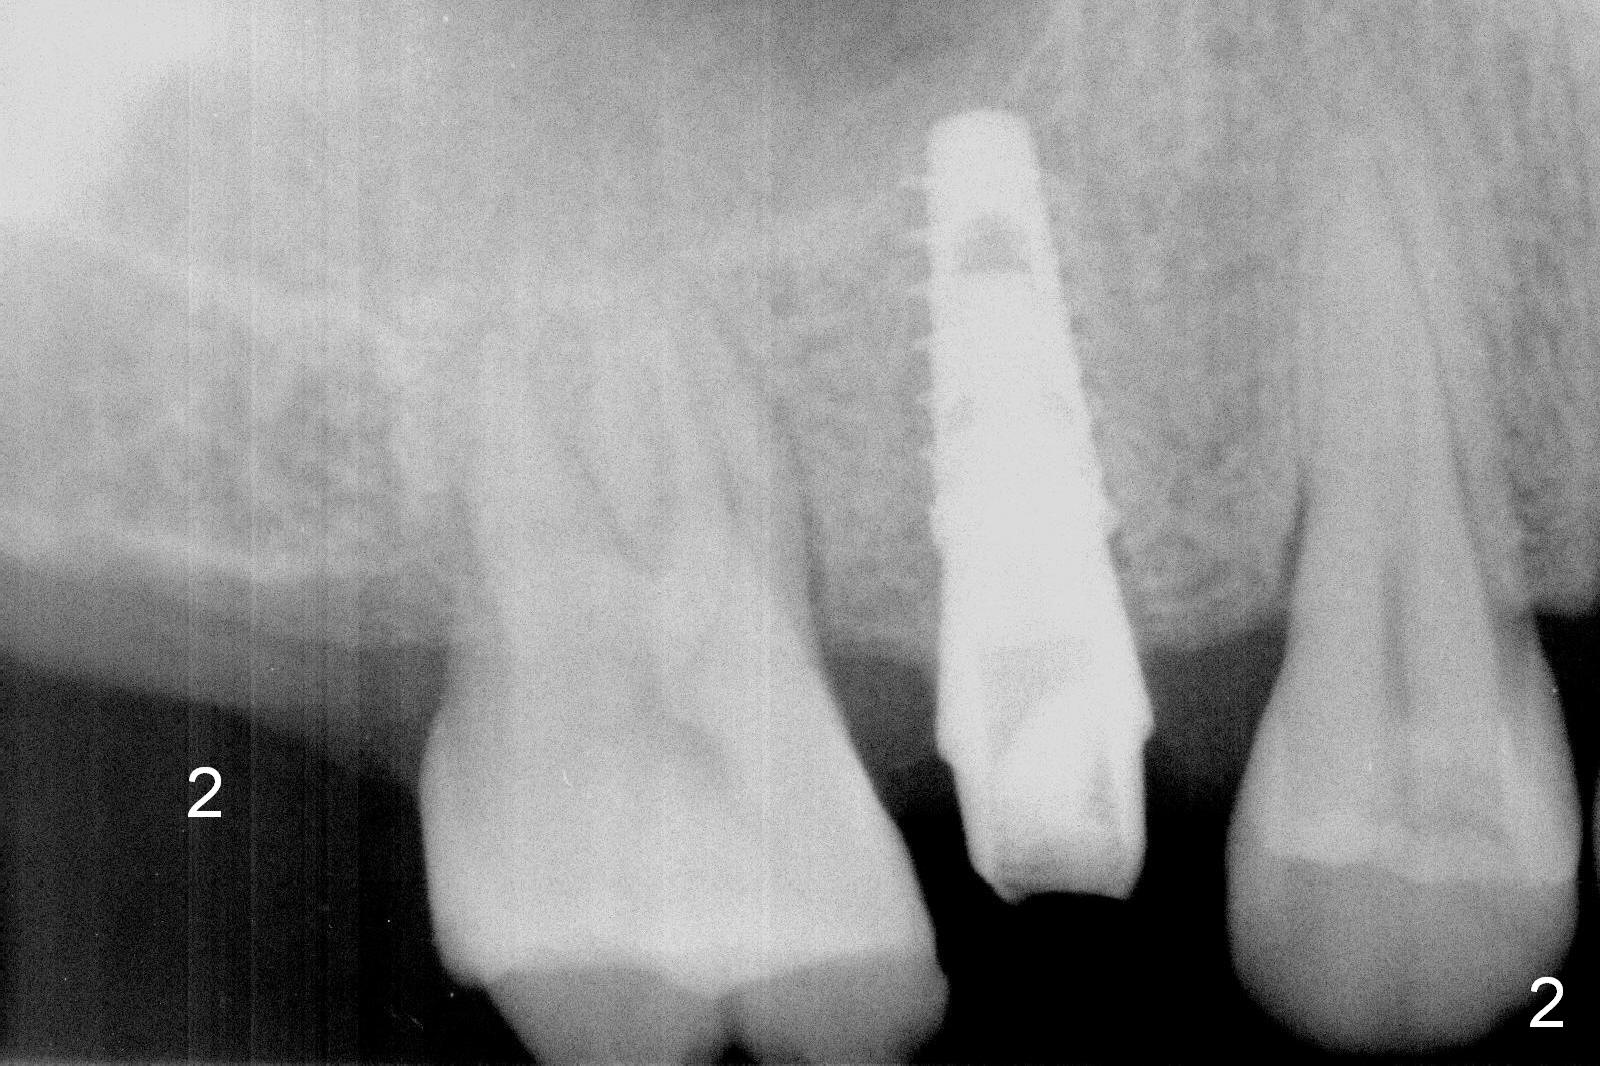

There is a tendency to drift osteotomy distally at the upper 2nd molar area when the 3rd molar is missing. Without a surgical stent, an implant spacer should be used constantly from the beginning (pilot drill) to the end (implant placement, Fig.3) for the site of #2 of the 47-year-old man (Fig.2). The tooth was extracted because of periodontitis and bruxism (Fig.1 (taken 5 years earlier)). Please measure the diameter of the handle of every instrument, including drill, expander and implant driver in advance (Fig.3 red lines). The center of the handle should be 5 mm from the distal surface of the 1st molar. If the diameter of the handle is 2 mm, the implant spacer is set to be 4 mm (Fig.3). For convenience of insertion (the edge of the spacer is wider than the center), use the 3.5 mm one. Take PA as early as possible and change position with a Lindamann bur accordingly. Prepare Magic Sinus Kit and separate IBS implant driver (in a pouch, not from a cassette).